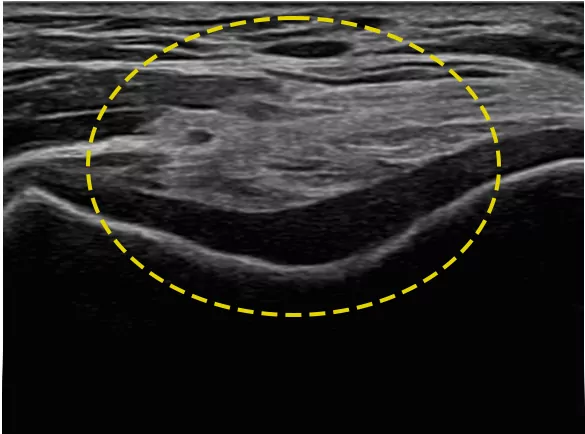

NerveTrack™ це функція, яка виявляє та надає інформацію про розташування ділянки нерва в режимі реального часу під час ультразвукового сканування.

NerveTrack™